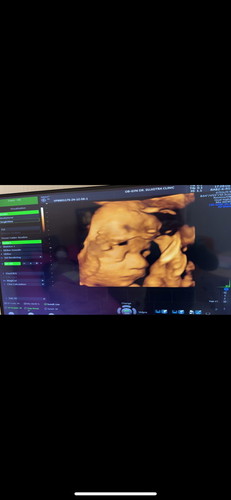

28+6ได้เห็นหน้าเจ้าจิ๋วชัดเจนแล้วค่ะ จมูกชัดมาก น้ำหนักน้อง 1,340กรัม ตามเกณฑ์ แม่บ้านอื่นน้ำหนักน้องเท่าไหร่กันบ้างค่ะ

บ้านนี้28+4 1400กรัมจ้า😁😁😁